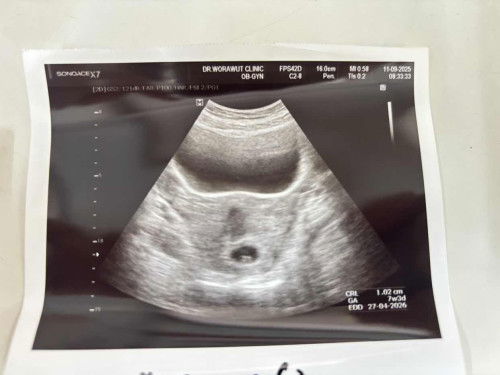

ท้อง7w3d ยังไม่พบคลื่นหัวใจ

พอดีวันนี้ไปซาวด์ คุณหมอบอกเจอถุงการตั้งครรภ์ และตัวเด็กประมาณ1 cm ได้ แต่ยังไม่พบคลื่นหัวใจ อีก1สัปดาห์นัดไปฟังอีกรอบ แบบนี้ปกติมั้ยคะ อายุครรภ์ขนาดนี้ปกติต้องเจอหัวใจแล้วมั้ยคะ ใครมีประสบการณ์บ้างคะ